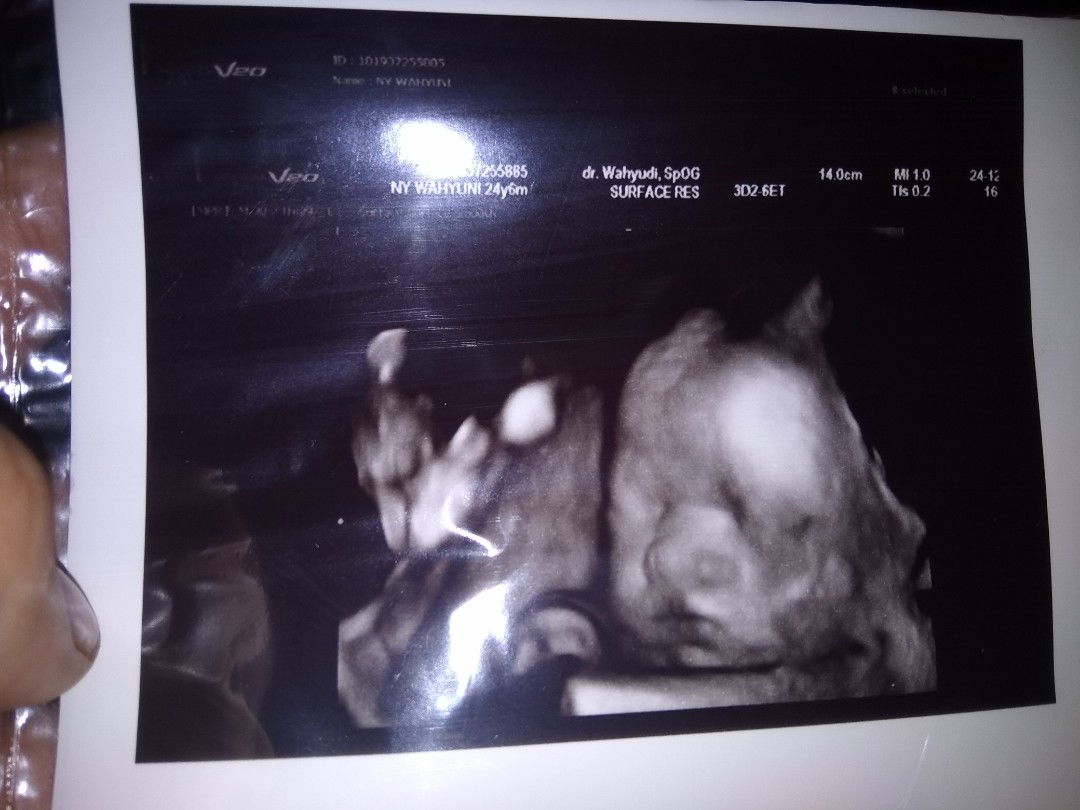

Assallamualaikum bunda, mw brbagi crita, ini hasil usg sya td sore, Hasilnya, baby ny saat ini lg sungsang bun, trus tali pusarnya lg kelilit. Doain normal lg ya bun? td di ajarin terapi jugak sama dokternya, Hpl maret 2020, ???